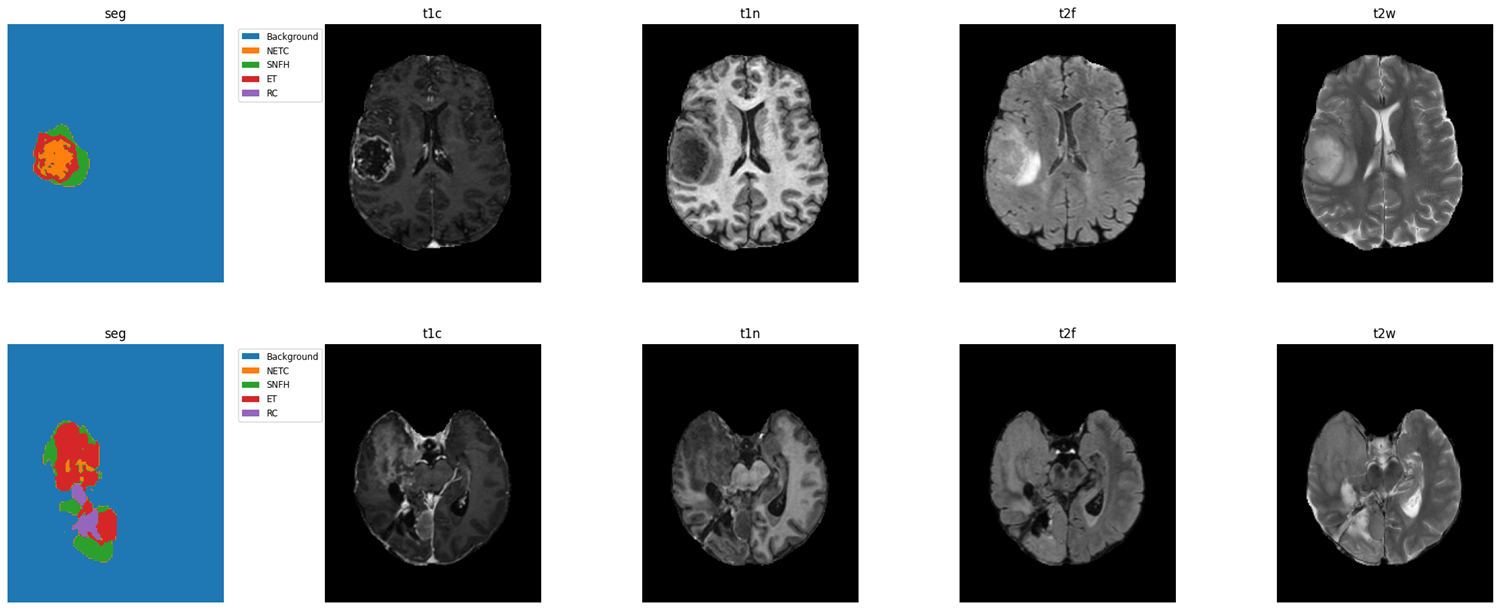

The data provided by the BraTS 2025 challenge is acquired over multiple institutions and includes routine pre- and post-treatment multi-parametric MRI (mpMRI) from patients diagnosed with diffuse gliomas resulting in total in 2877 cases. Each case in the dataset has four co-registered mpMRI modalities in NIfTI format: native T1-weighted (t1n), post-contrast T1-weighted (t1ce), T2-weighted (t2w), and T2 FLAIR (t2f). All volumes are isotropically resampled to a resolution of 1mm3 with dimensions (182,218,182). Corresponding annotations (Figure 1) consist of four tumor subregions to which we refer as ’Tumor Classes’ from now on:

• Non-enhancing tumor core (NETC)- the necrosis and cysts within the tumor

• Surrounding non-enhancing FLAIR hyperintensity (SNFH)- edema, infiltrating tumor, and post-treatment changes

• Enhancing tumor (ET)- regions of active tumor

• Resection cavity (RC) -recent and chronic resection cavities (only in post-treatment scans)

Refer to caption

Figure 1: Central axial slice of pre-treatment scans(upper row) and post-treatment scans (lower row)